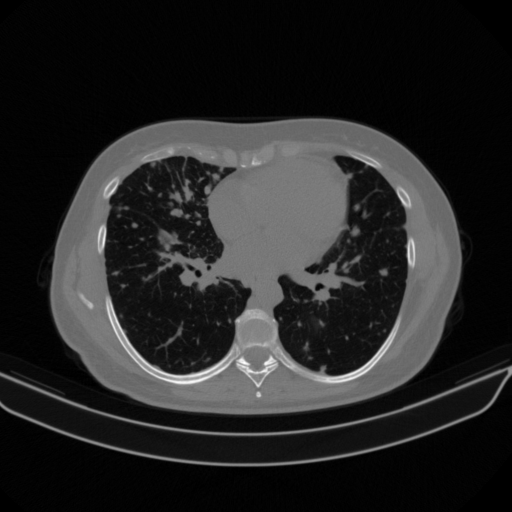

Slice 70 Targeting Evaluation

Slice: Slice_70

Conversion: NATIVE β†’ VENOUS

Generated VENOUS CT scan (A→B translation)

No window - Raw intensity values

Lung window (WL -600, WW 1500 β†’ Low βˆ’1350, High +150)

Mediastinum window (WL 40, WW 400 β†’ Low βˆ’160, High +240)

Targeted Slice 70 - Mediastinum Window Analysis (Generated vs Real Venous)

0.762

Mediastinum SSIM

47.9

Mediastinum RMSE

17.1

Mediastinum MAE

Average Mediastinum Window Metrics Across All Slices (133 slices) - Generated vs Real Venous

0.740

Mediastinum SSIM (Avg)

46.9

Mediastinum RMSE (Avg)

17.0

Mediastinum MAE (Avg)